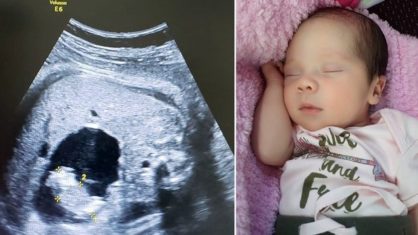

Na Colômbia, Itzmara nasceu

com uma condição muito rara conhecida como “feto no feto”. Essa condição

acontece em cerca de um em cada 500 mil nascimentos.

O caso de Itzmara foi ainda

mais incomum, pois os médicos identificaram o feto dentro do bebê ainda durante

a gravidez, conforme explicou o obstetra Miguel Parra-Saavedra. O obstetra

O médico anterior de Monica

acreditava que o bebê tinha um cisto no fígado. Mas essa teoria foi por água

abaixo quando Miguel Parra, usando um Doppler colorido e imagens de ultrassom

3D/4D, foi capaz de ver que o espaço cheio de fluido, na verdade, continha um

bebê minúsculo, sustentado por um cordão umbilical separado que extraia sangue,

e conectado ao intestino do gêmeo maior.

Com 37 semanas de gravidez,

Itzmara já pesava cerca de três quilos e os médicos decidiram fazer o parto

cesariana, pois temiam que a gêmea interna esmagasse seus órgãos abdominais. No

dia seguinte após o parto, o gêmeo fetal foi removido por cirurgia

laparoscópica. O obstetra ainda contou que, às vezes, esses fetos são

diagnosticados erroneamente como teratoma, um tumor que pode conter ossos,

tecido muscular e cabelo.

O doutor afirmou que Itzmara

está bem. “Ela tem uma pequena cicatriz em seu abdômen, mas é um bebê normal

agora, exceto que o mundo inteiro está falando sobre ela”, finalizou.